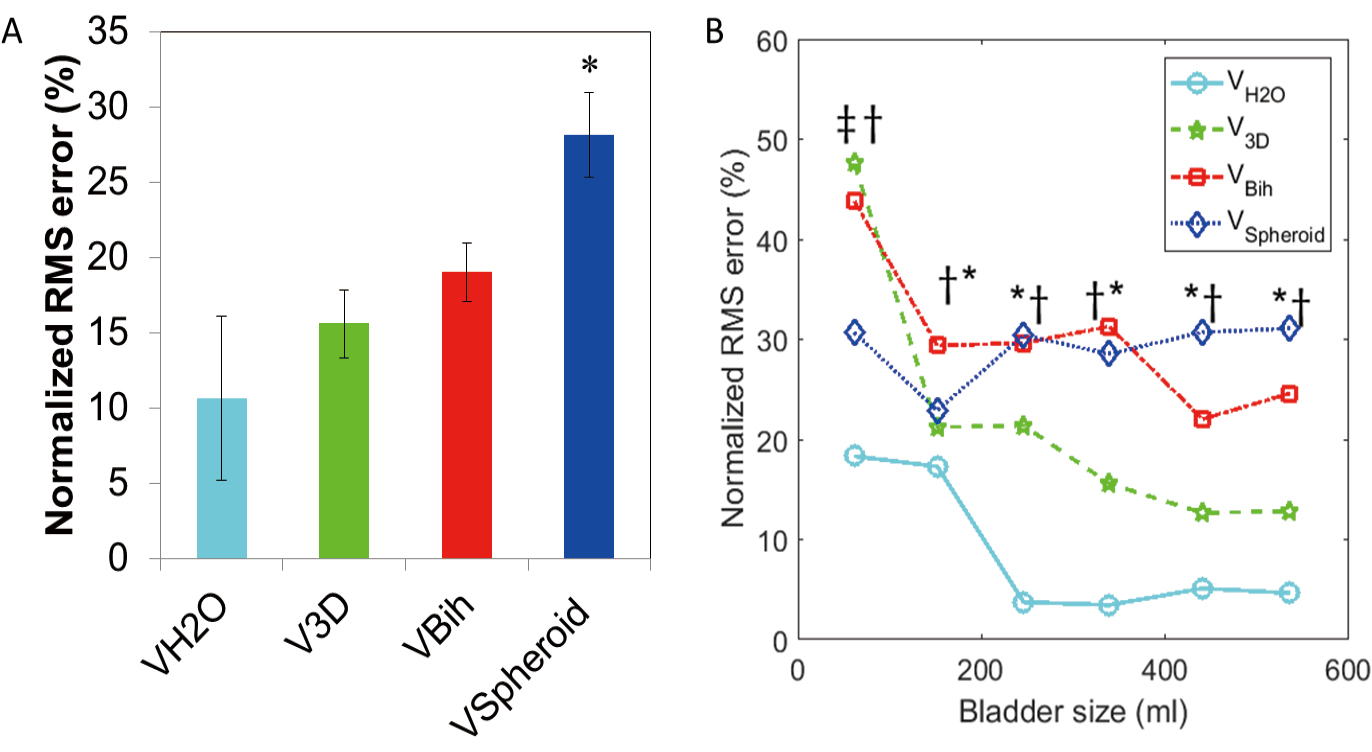

Results: Based on linear regression analysis, both Vbih and V3D were fairly accurate estimators of Vcontrol, but V3D was more precise. Vspheroid significantly underestimated Vcontrol.

Conclusions: Although the Vbih and V3D methods were more accurate than the more-commonly used Vspheroid method for measuring bladder volumes during UD, the V3D method was the most precise and could best account for non-uniform bladder geometries. Therefore, the V3D method may represent the best tool required for the continued development of non-invasive methods to diagnose OAB and other forms of voiding dysfunction.